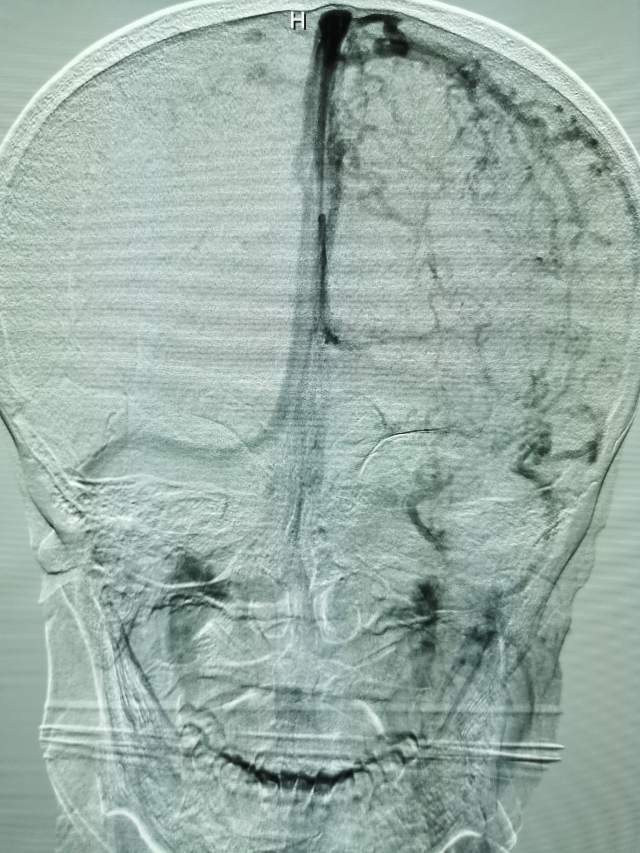

鉴于老人家体质虚弱,走路不方便,疫情期间,家人又不方便陪同,我们采用最微创的远侧桡动脉入路为老人家做了进一步检查,血管真的很扭哈,老人家也听不清楚,检查期间动来动去的,结果发现:下水道(深浅静脉系统有血栓堵塞)不通畅哦,次日给予了药物调整。治疗3天后,老人家听力明显改善,可以和医生自由交流,下床走路也如履平地,完全换了一个人哈~~~